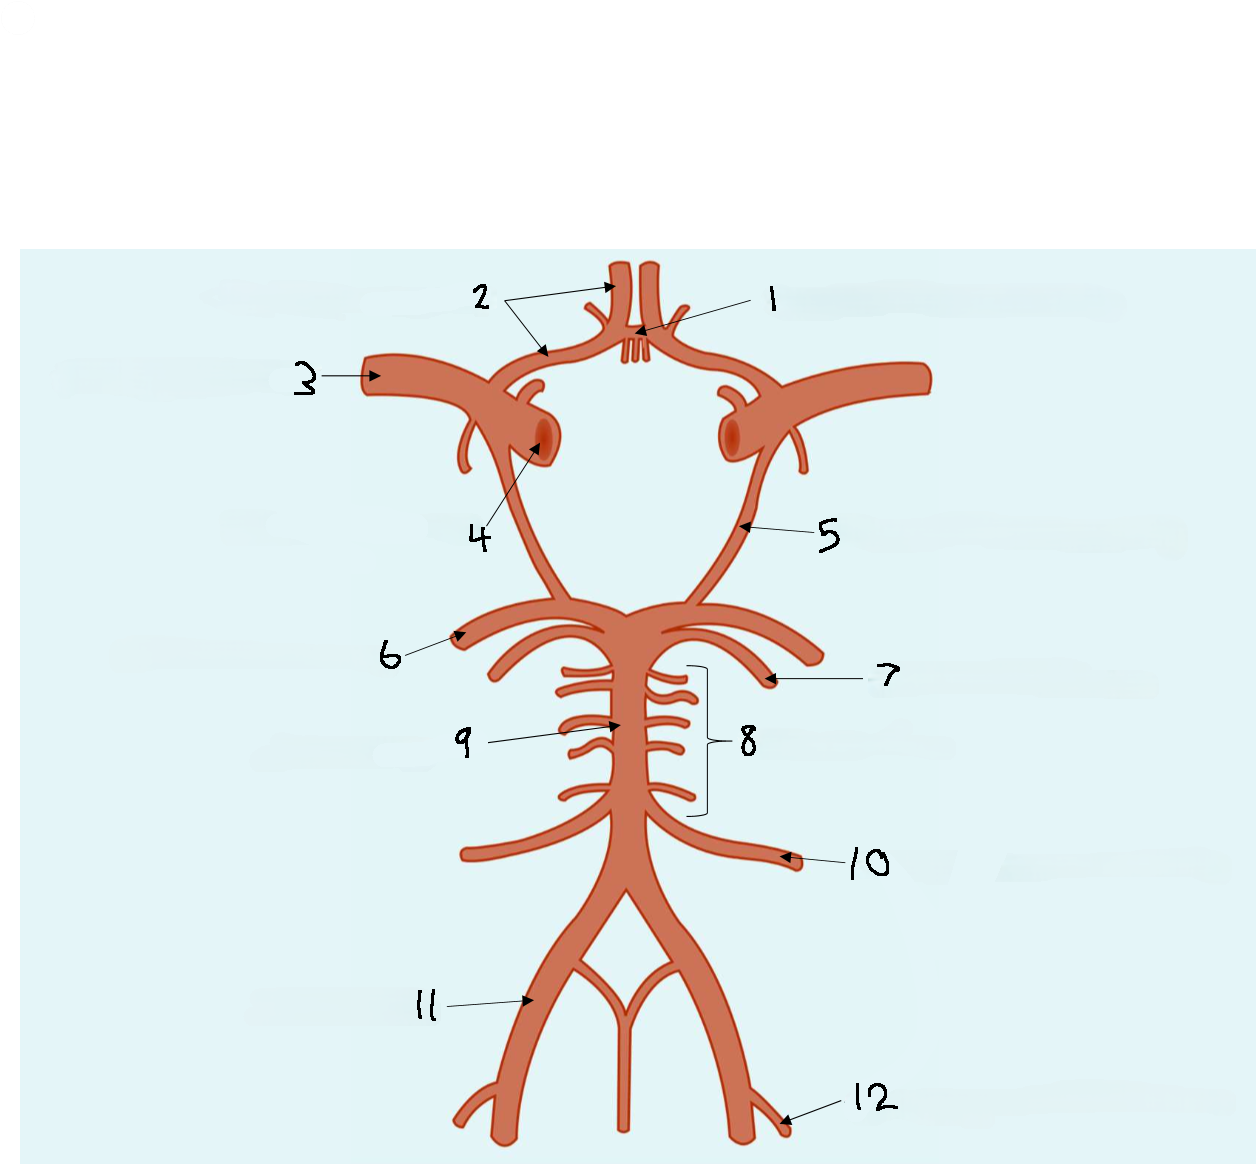

What is 1?

anterior communicating artery

What is 2?

anterior cerebral artery

What is 3?

middle cerebral artery

What is 4?

internal carotid artery

What is 5?

posterior communicating artery

What is 6?

posterior cerebral artery

What is 7?

superior cerebellar artery

What is 8?

pontine arteries

What is 9?

basilar artery

What is 10?

anterior inferior cerebellar artery

What is 11?

vertebral artery

What is 12?

posterior inferior cerebellar artery